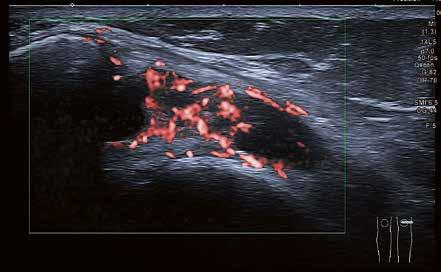

Hochauflösender Ultraschall in der Sportpraxis

Wie kamen Sie zur Sonographie?